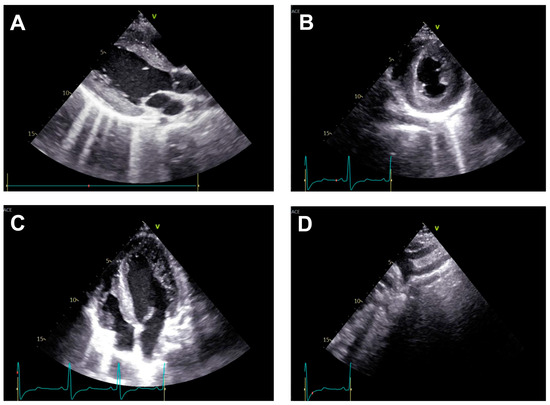

Endovascular Repair of Thoracic Aortic Atresia in Adults: A Narrative Review of a Rare Entity and Emerging Technique

Thoracic aortic atresia in adults represents a rare and extreme manifestation of aortic coarctation, marked by complete luminal occlusion and frequently compensated by extensive collateral circulation. This narrative review critically evaluates existing literature and institutional experience concerning surgical and endovascular repair strategies for [...] Read more.

Thoracic aortic atresia in adults represents a rare and extreme manifestation of aortic coarctation, marked by complete luminal occlusion and frequently compensated by extensive collateral circulation. This narrative review critically evaluates existing literature and institutional experience concerning surgical and endovascular repair strategies for aortic atresia, synthesizing evidence from related aortic arch pathologies due to the absence of direct comparative studies. Both treatment modalities—open surgical repair and catheter-based recanalization with stenting—have evolved significantly, presenting distinct advantages and limitations influenced by patient anatomy, age, and comorbidities. While surgical repair remains the standard for neonates, infants, and complex cases due to superior long-term durability and blood pressure control, endovascular procedures using chronic total occlusion technique and covered stents offer less invasive alternatives with rapid recovery, particularly in adults with suitable anatomic characteristics. The review highlights procedural considerations, including technical approaches, stent selection, and potential complications such as restenosis, hypertension, and vascular injury. Individualized, multidisciplinary decision-making remains essential, with shared consensus guiding therapy in the absence of randomized trials. The article identifies critical gaps in knowledge, emphasizing the need for multicenter, long-term studies and technological advances—including hybrid and personalized strategies for optimal management and for improving outcomes in this challenging congenital condition. Full article

Show Figures

Figure 1